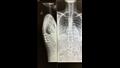

أُصيبت المرأة البالغة من العمر 23 سنة، بكسور في الظهر والحوض والساقين، إضافة إلى ذلك، تحطم كاحلها بعد سقوطها على رصيف خرساني.

وخشي الأطباء من إصابة صوفي بالشلل الدائم بسبب خطورة إصاباتها.